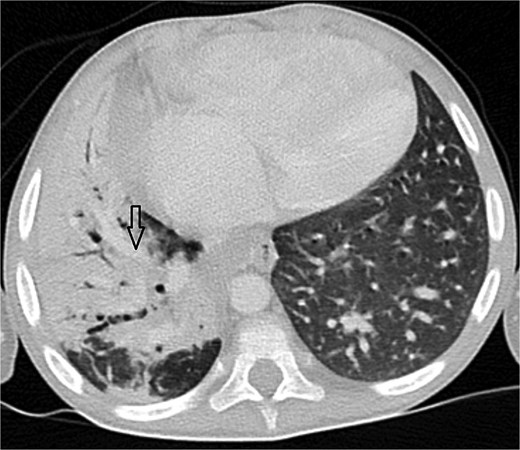

Axial CT angiogram in lung window demonstrating right lower-lobe consolidation and volume loss with mediastinal shift, consistent with pneumonia and compression by the pseudoaneurysm.

Urgent transthoracic echocardiography demonstrated a large echodense mass in the right hemithorax, compression of the right atrium and reduced flow through the right-sided shunt. Computed tomography angiography (CTA) confirmed a massive saccular pseudoaneurysm (≈8 × 7 × 6 cm) arising from the anastomosis between the right subclavian artery and the mBTTS graft, completely thrombosed without active contrast extravasation (Fig. 1). There was complete thrombotic occlusion of the right pulmonary artery, right lung collapse due to extrinsic compression and right lower-lobe consolidation consistent with pneumonia (Fig. 2). CTA also revealed left isomerism with central liver and polysplenism (Fig. 3) and a horseshoe kidney (Fig. 4), suggesting a previously unrecognized polymalformative syndrome.